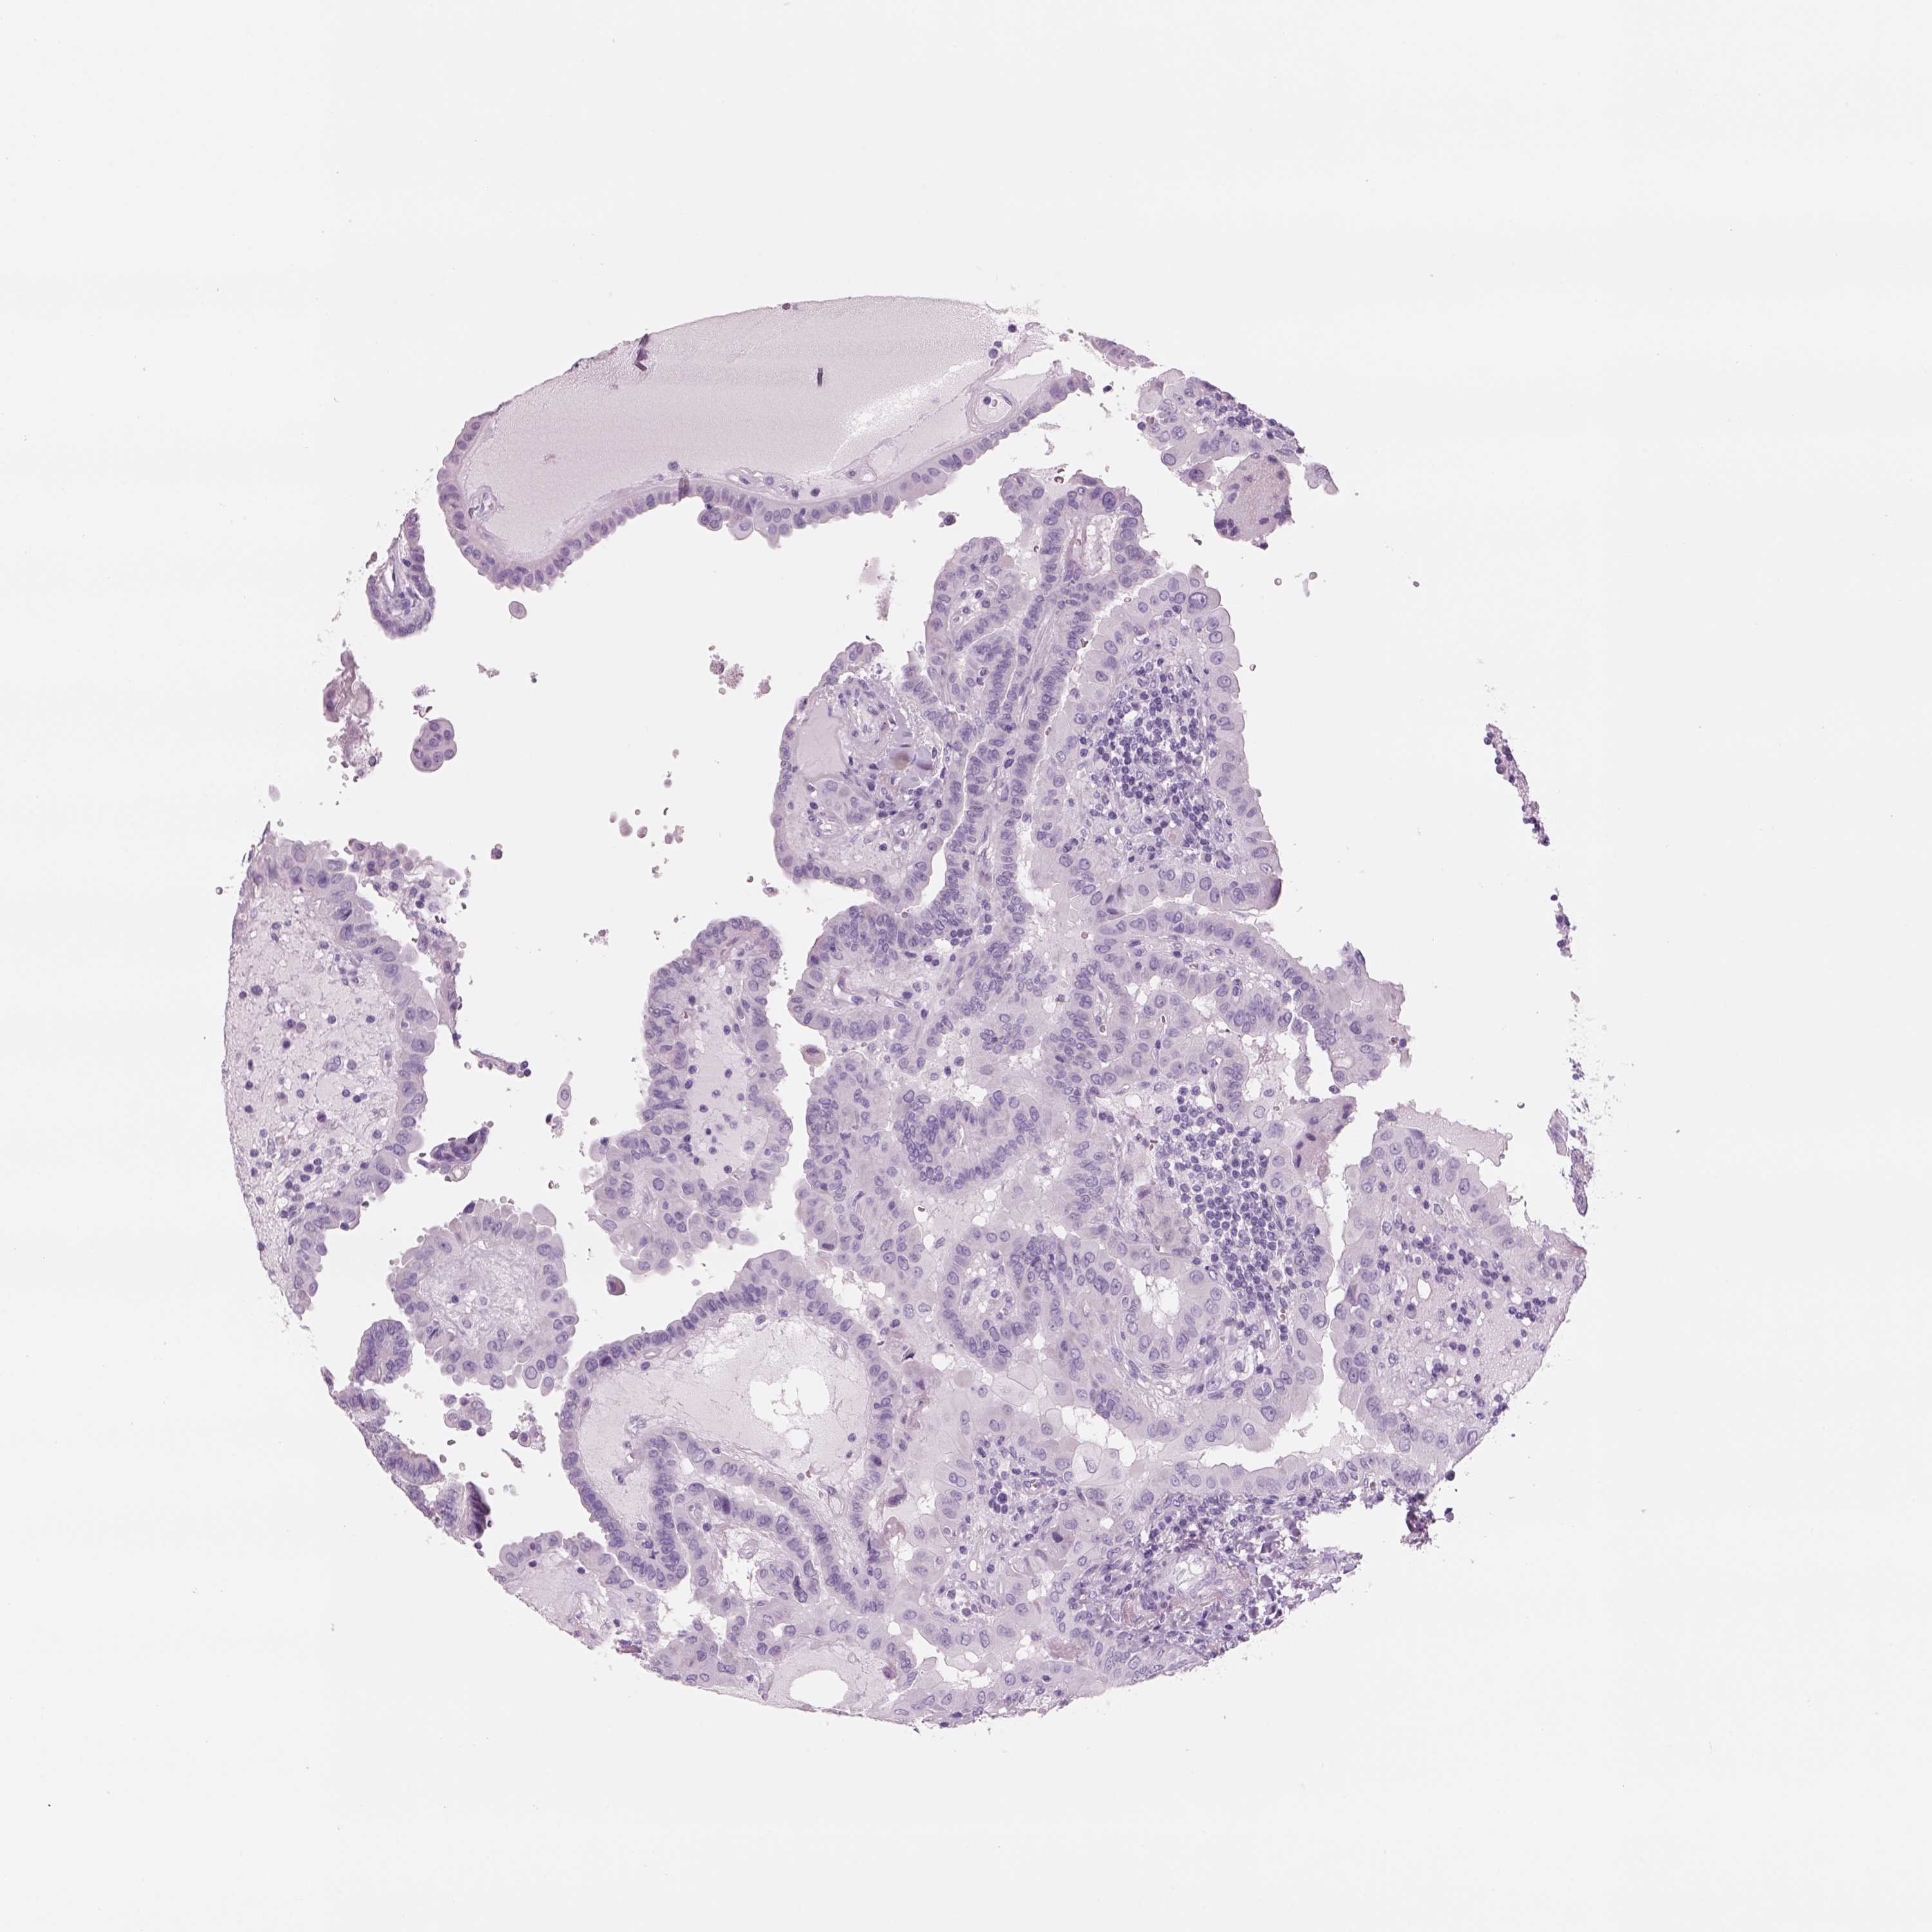

THYROID CANCER - Protein expressioni

A mouse-over function shows sample information and annotation data. Click on an image to view it in a full screen mode. Samples can be filtered based on level of antibody staining by selecting one or several of the following categories: high, medium, low and not detected. The assay and annotation is described here.

Note that samples used for immunohistochemistry by the Human Protein Atlas do not correspond to samples in the TCGA dataset.

Antibody stainingi

Antibody staining in the annotated cell types in the current human tissue is reported as not detected, low, medium, or high, based on conventional immunohistochemistry profiling in selected tissues. This score is based on the combination of the staining intensity and fraction of stained cells.

Each image is clickable and will lead to virtual microscopy that enables deeper exploration of all samples and also displays staining intensity scores, fraction scores and subcellular localization as well as patient and tissue information for each sample.

Antibody HPA013440

Antibody CAB022486

Antibody CAB034887

Antibody CAB034888

Staining

High

Medium

Low

Not detected

Intensity

Strong

Moderate

Weak

Negative

Quantity

>75%

75%-25%

<25%

None

Location

Nuclear

Cytoplasmic/membranous

Cytoplasmic/membranous,nuclear

Papillary adenocarcinoma, NOS

Follicular adenoma carcinoma, NOS